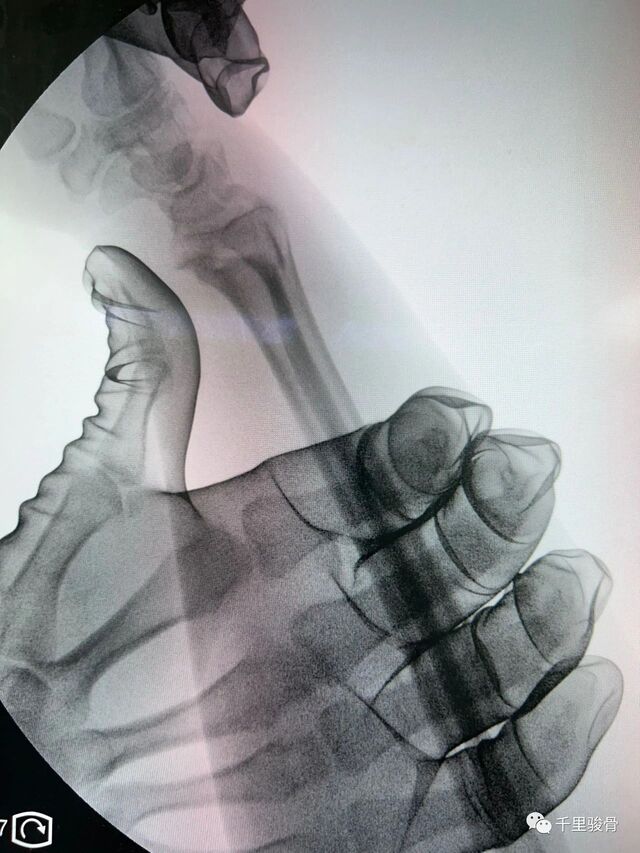

河北省三院的刘月驹:

要有舍命相搏的勇气

微信图片_20240102194826.jpg

微信图片_20240102194834.jpg

麻醉下透视复位